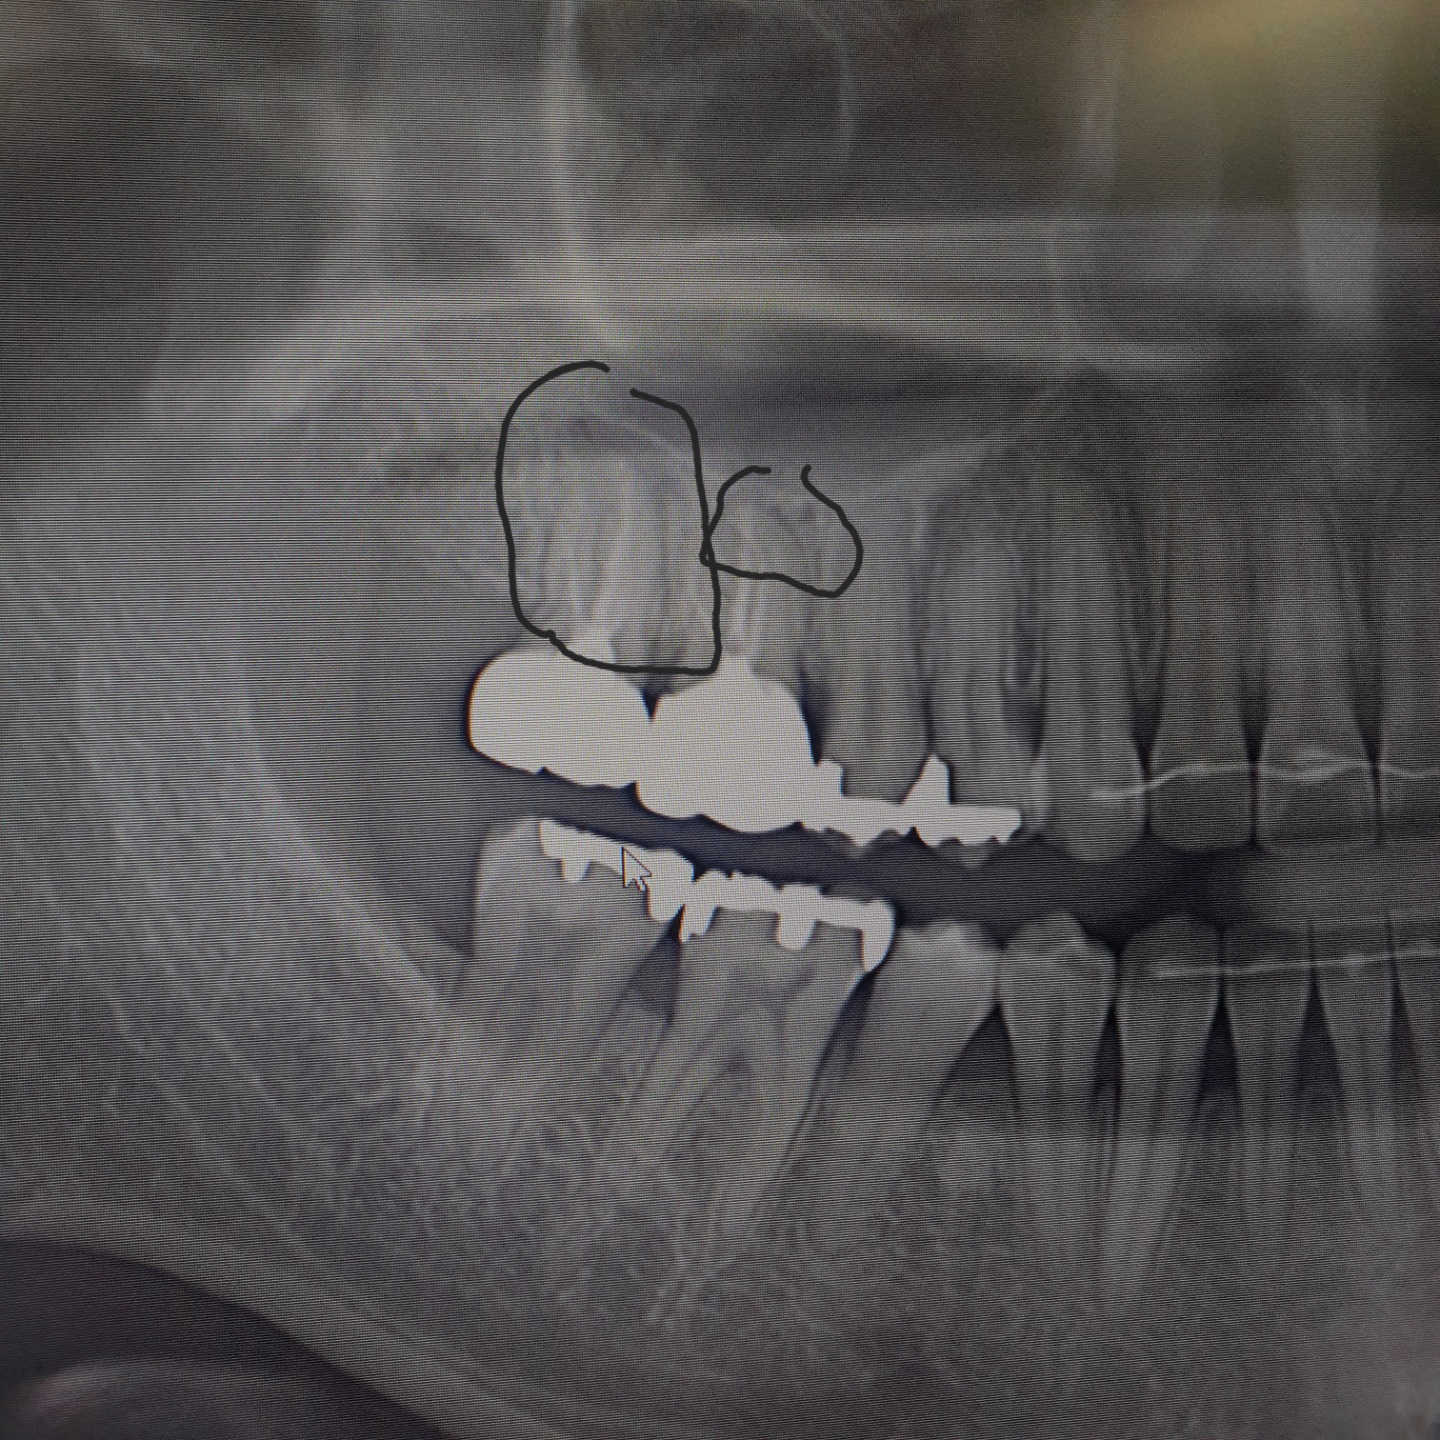

외진곳에 살고있어서 버스타고 30분씩 가야 치과가 겨우 하나 있는 곳에 살고있습니다. 어금니 윗쪽이 아프고 머리가 아파서 치과에 갔는데요. 어느 병원에서는 이정도는 전혀 신경치료나 임플란트같은건 안해도 된다고 하시네요. 그리고 잇몸 염증보다는 이빈후과에 가서 머리쪽과 이빨과 연결된 어딘가가 아플수도 잇으니 이빈후과를 가라고 하시더군요 그래서 오늘 다른 치과에 가서 엑스레이를 찍어봤는데 거기서는 임플란트를 해야 할것 같다고 하시네요. 사진에 있는 검은색 테두리 안쪽 부분과, 주황색 네모 부분 안쪽이 염증으로 보이는 부분인데요. 주황색으로 테두리 친 치과는 이건 염증이 아니라 하시고, 검은색으로 체크해주신 병원은 염증이라고 하시네요. 이미 신경치료를 했던 이빨이기에 더이상 신경치료는 의미가 없고 임플란트를 하라고 하십니다. 비용은 총 100만원 정도구요. (이빨 하나에) 100만원이 작은 돈이 아니라 다른 병원 또 가보고 싶긴한데... 궁금해서 홍차넷에 한번 물어보고 싶습니다. 0